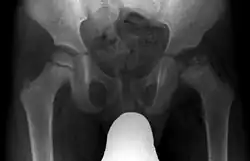

Radiograph of a person with Legg–Calvé–Perthes disease

X ray of deformity by Legg–Calvé–Perthes disease of the right hip (left side of X-ray)